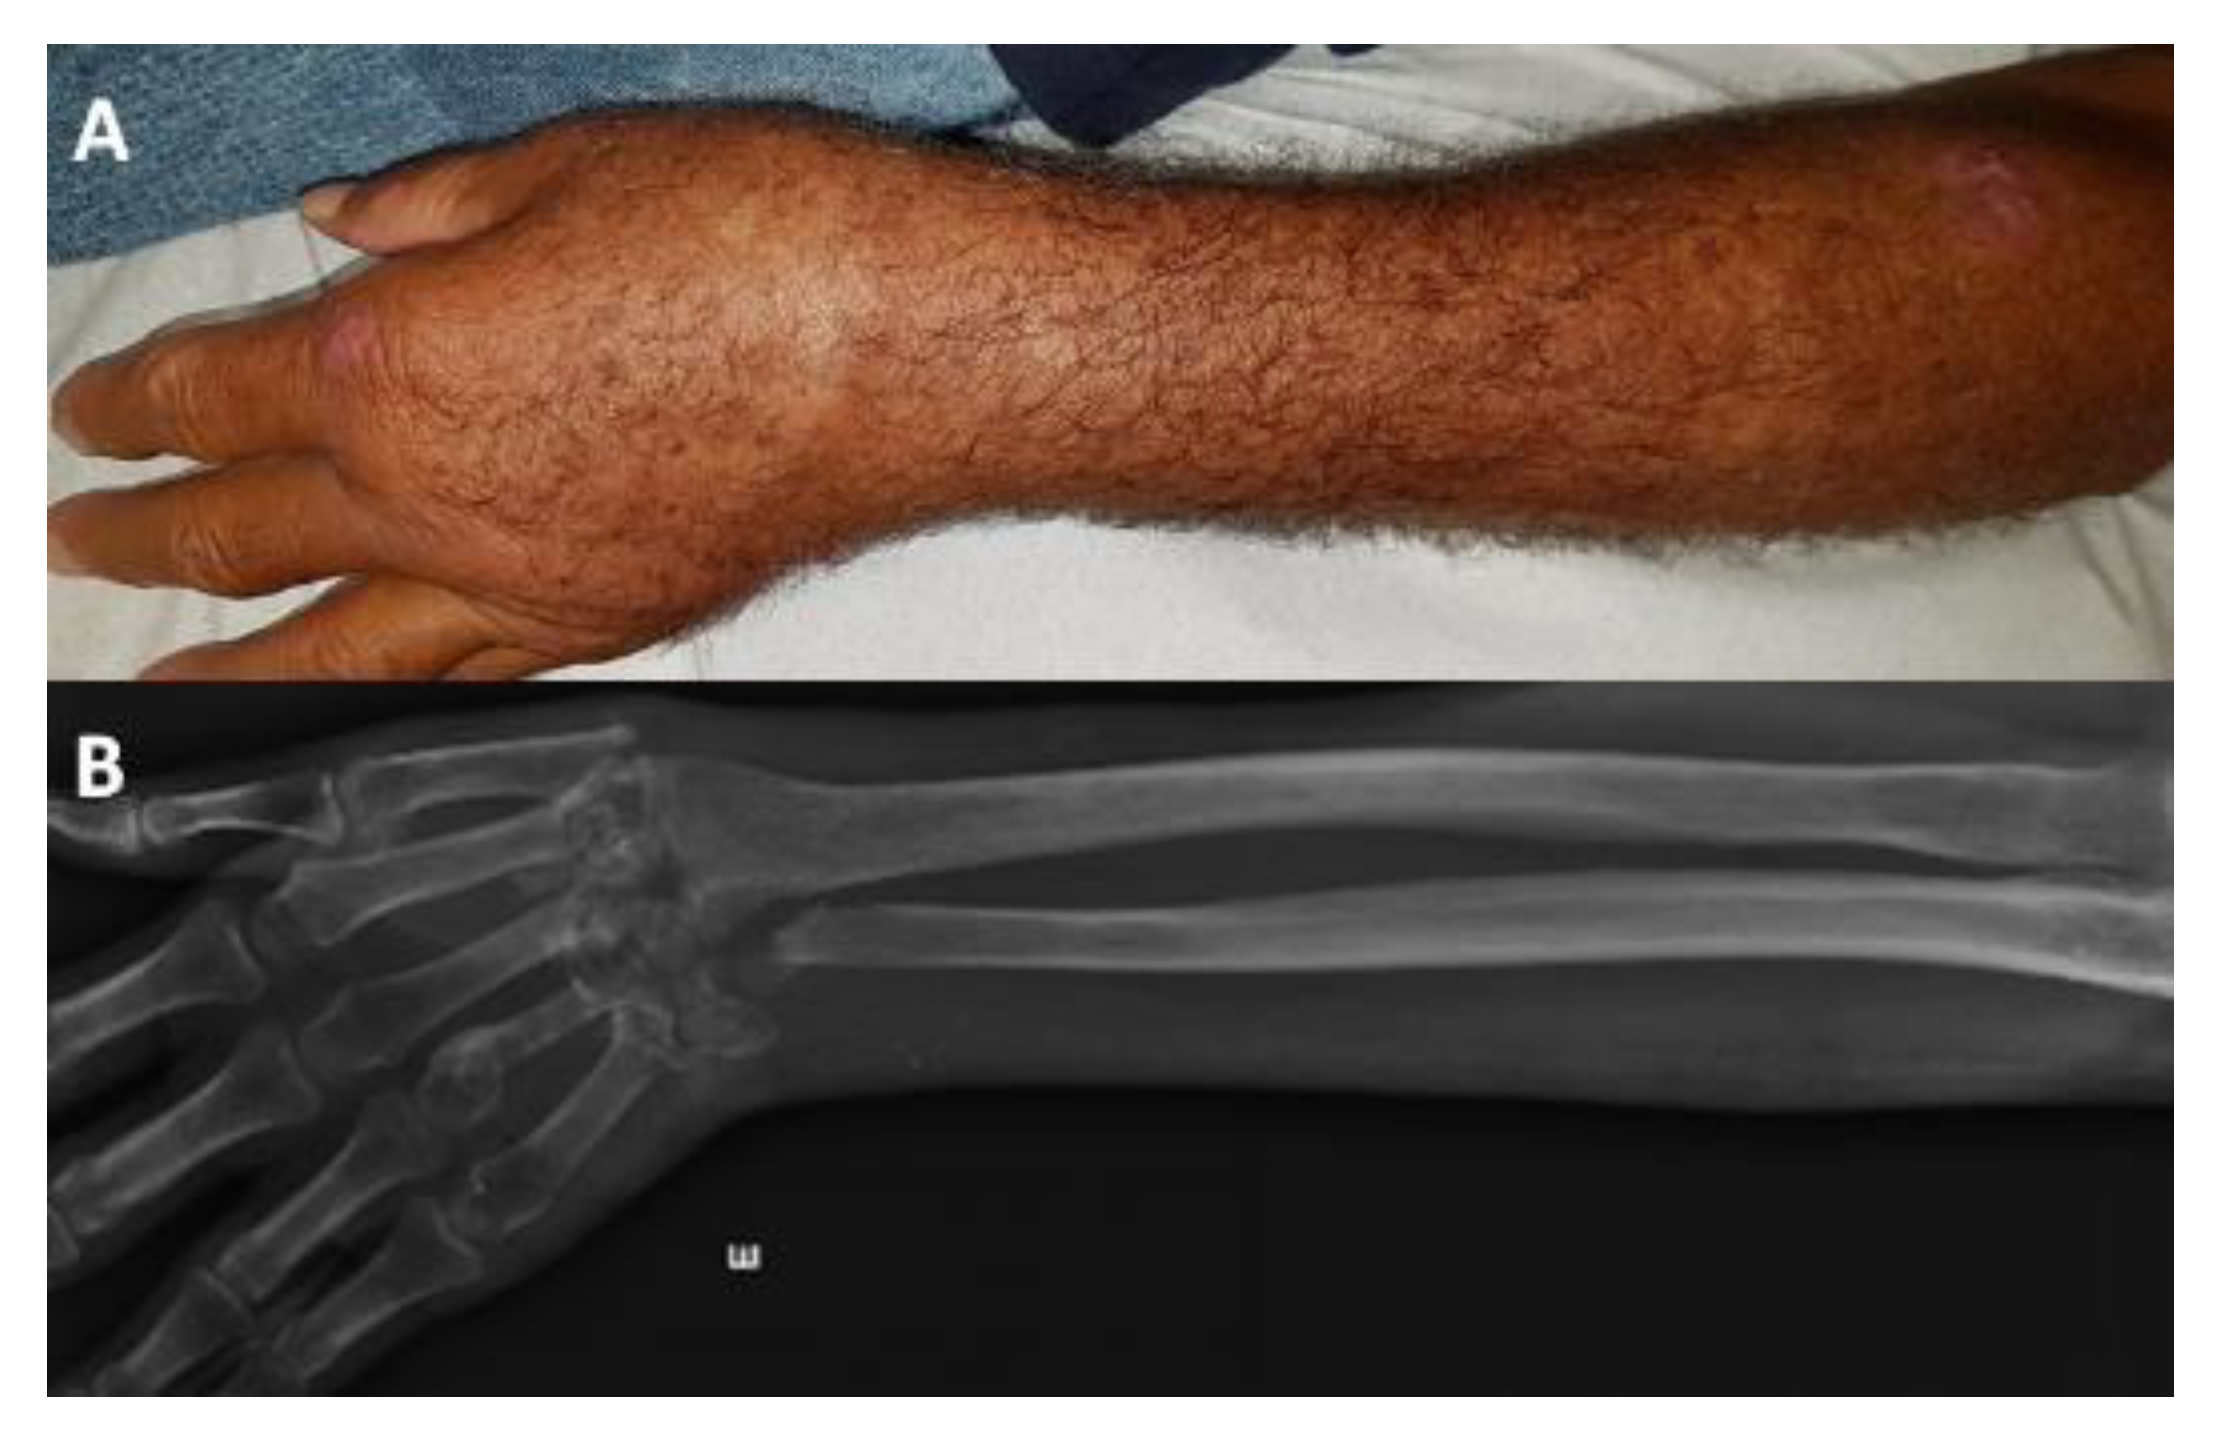

| Clinical presentation | Lymphocutaneous | 562 (62) |

| Fixed cutaneous | 233 (25.7) | |

| Cutaneous disseminated | 81 (8.9) | |

| Extracutaneous/Disseminated b | 30 (3.3) | |

| Organs affected c | Skin | 900 (99.3) |

| Osteoarticular | 19 (2.1) | |

| Contiguity unifocal extracutaneous sporotrichosis | lymphocutaneous + osteomyelitis | 2 |

| fixed cutaneous + osteomyelitis | 2 | |

| lymphocutaneous + osteomyelitis + synovitis | 1 | |

| lymphocutaneous + synovitis | 3 | |